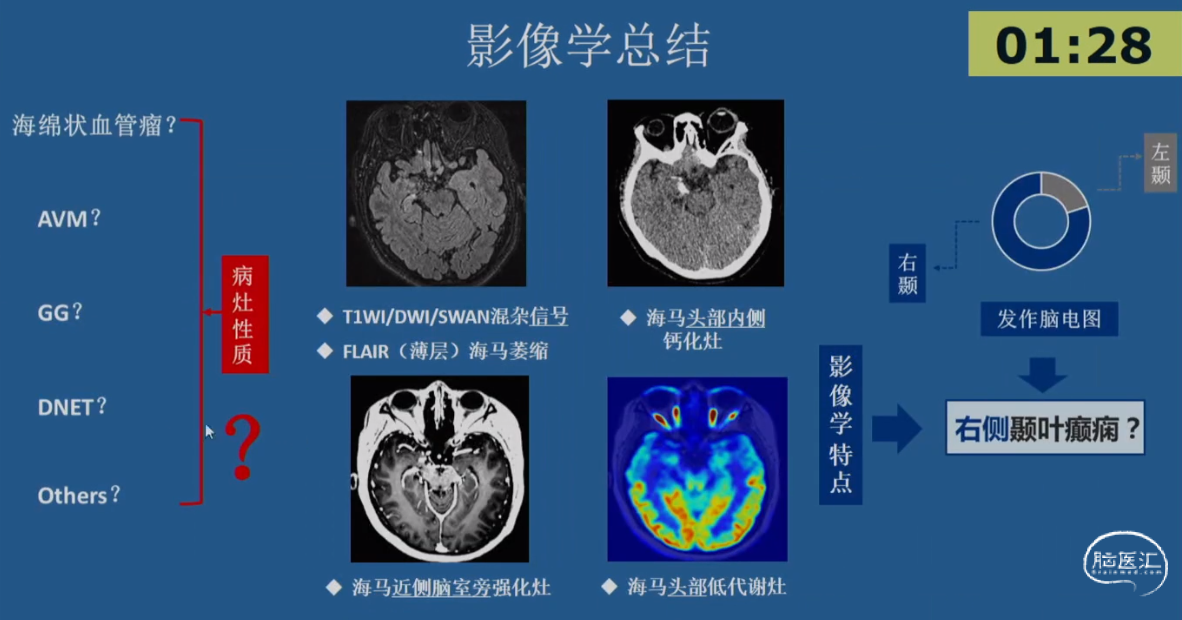

病例示例3 -简要病史

•患者,女性,20岁,右利手

•起病年龄:出生4月

•主要发作形式:伴有知觉受累的局灶性发作

-发作主要表现:发作前偶伴心悸、胸闷→后出现意识丧失伴眼神呆滞→数秒后出现身体向各方向不自主扭转,伴喉部发声(无四肢抽搐表现)→发作持续5-10min后意识恢复→发作后无头痛、头晕等不适

-【出生4月起】:初始发作频率1次/天,服用CBZ后发作可控;

-【12岁起】:发作频率再次↑为1次/天,加用药物后发作控制于5-10次/年;

-【19岁起】:多药联用控制不佳,发作频繁时可达3-4次/天,至少2-3次/月

•20岁时AEDs服用:CBZ 0.2g tid + LTG 100mg bid +CZP 0.5mg qn po

•既往史及家族史无殊,无热性惊厥史

•出生史:剖腹产,无早产、难产史,生长发育同同龄人;学历中专

•认知功能测评:MMSE 27分(延迟记忆-3),MoCA 27分(抽象-1,延迟回忆-2);WAIS-RC IQ 100分(语言IQ 92分;操作IQ 112分)

•情绪测评:HAMA 9分(轻度焦虑),HAMD 8分(轻度抑郁)

01.初步评估:

影像学表现:2018-03-05 MRI 常规MRI阴性

02.发作期评估

03.SEEG手术评估

04.手术预后及结果

行右侧前颞叶切除+海马杏仁核切除术(中山医院神经外科 胡凡 李宸)

术后影像

结构性病因诊断

•神经节细胞胶质瘤Gangliogliomas(GG)

•归类:神经元和神经元-神经胶质肿瘤类,WHO Ⅰ级

结构性病因诊断

•局灶性皮质发育不良(FCD)Ⅲb型